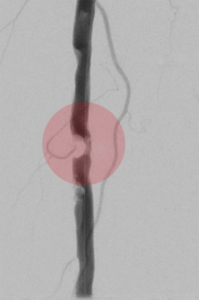

3. Stentimplantation – Einsetzen eines Stentes/ Gefäßstütze

Nach der Gefäßweitung kann durch Einrisse in den inneren Ablagerungen oder durch die Elastizität der Gefäßwand die Weitung nur ungenügend erfolgreich sein. Zur Stabilisierung des Befundes wird dann in diese Gefäßregion ein Stent eingesetzt. Dieser besteht aus einem feinen starren oder flexiblen Edelmetallgeflecht und kann auch mit Medikamenten gegen die Arteriosklerose oder zur Verhinderung der Bildung von Blutgerinnseln beschichtet sein.

Unter bestimmten Bedingungen, v.a. bei Verletzungen der Gefäße mit daraus resultierender Blutung oder lokalen Gefäßerweiterungen, werden Stents mit einer Ummantelung eingesetzt, die die Gefäßwand abdichten oder die Erweiterung überbrücken.